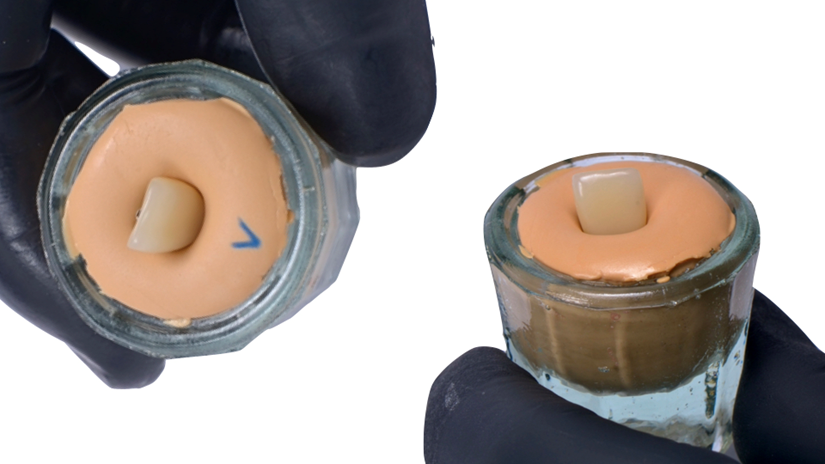

O caso foi conduzido com planejamento cuidadoso, moldagens analógicas e provas clínicas. A reabilitação foi finalizada com a instalação de uma coroa metalocerâmica parafusada, garantindo estética, funcionalidade e reversibilidade do conjunto protético.

Esse protocolo evidencia como a seleção correta do pilar protético, respeitando angulação e diâmetro adequados, pode contornar limitações anatômicas e transformar um caso potencialmente desfavorável em um resultado previsível e satisfatório.